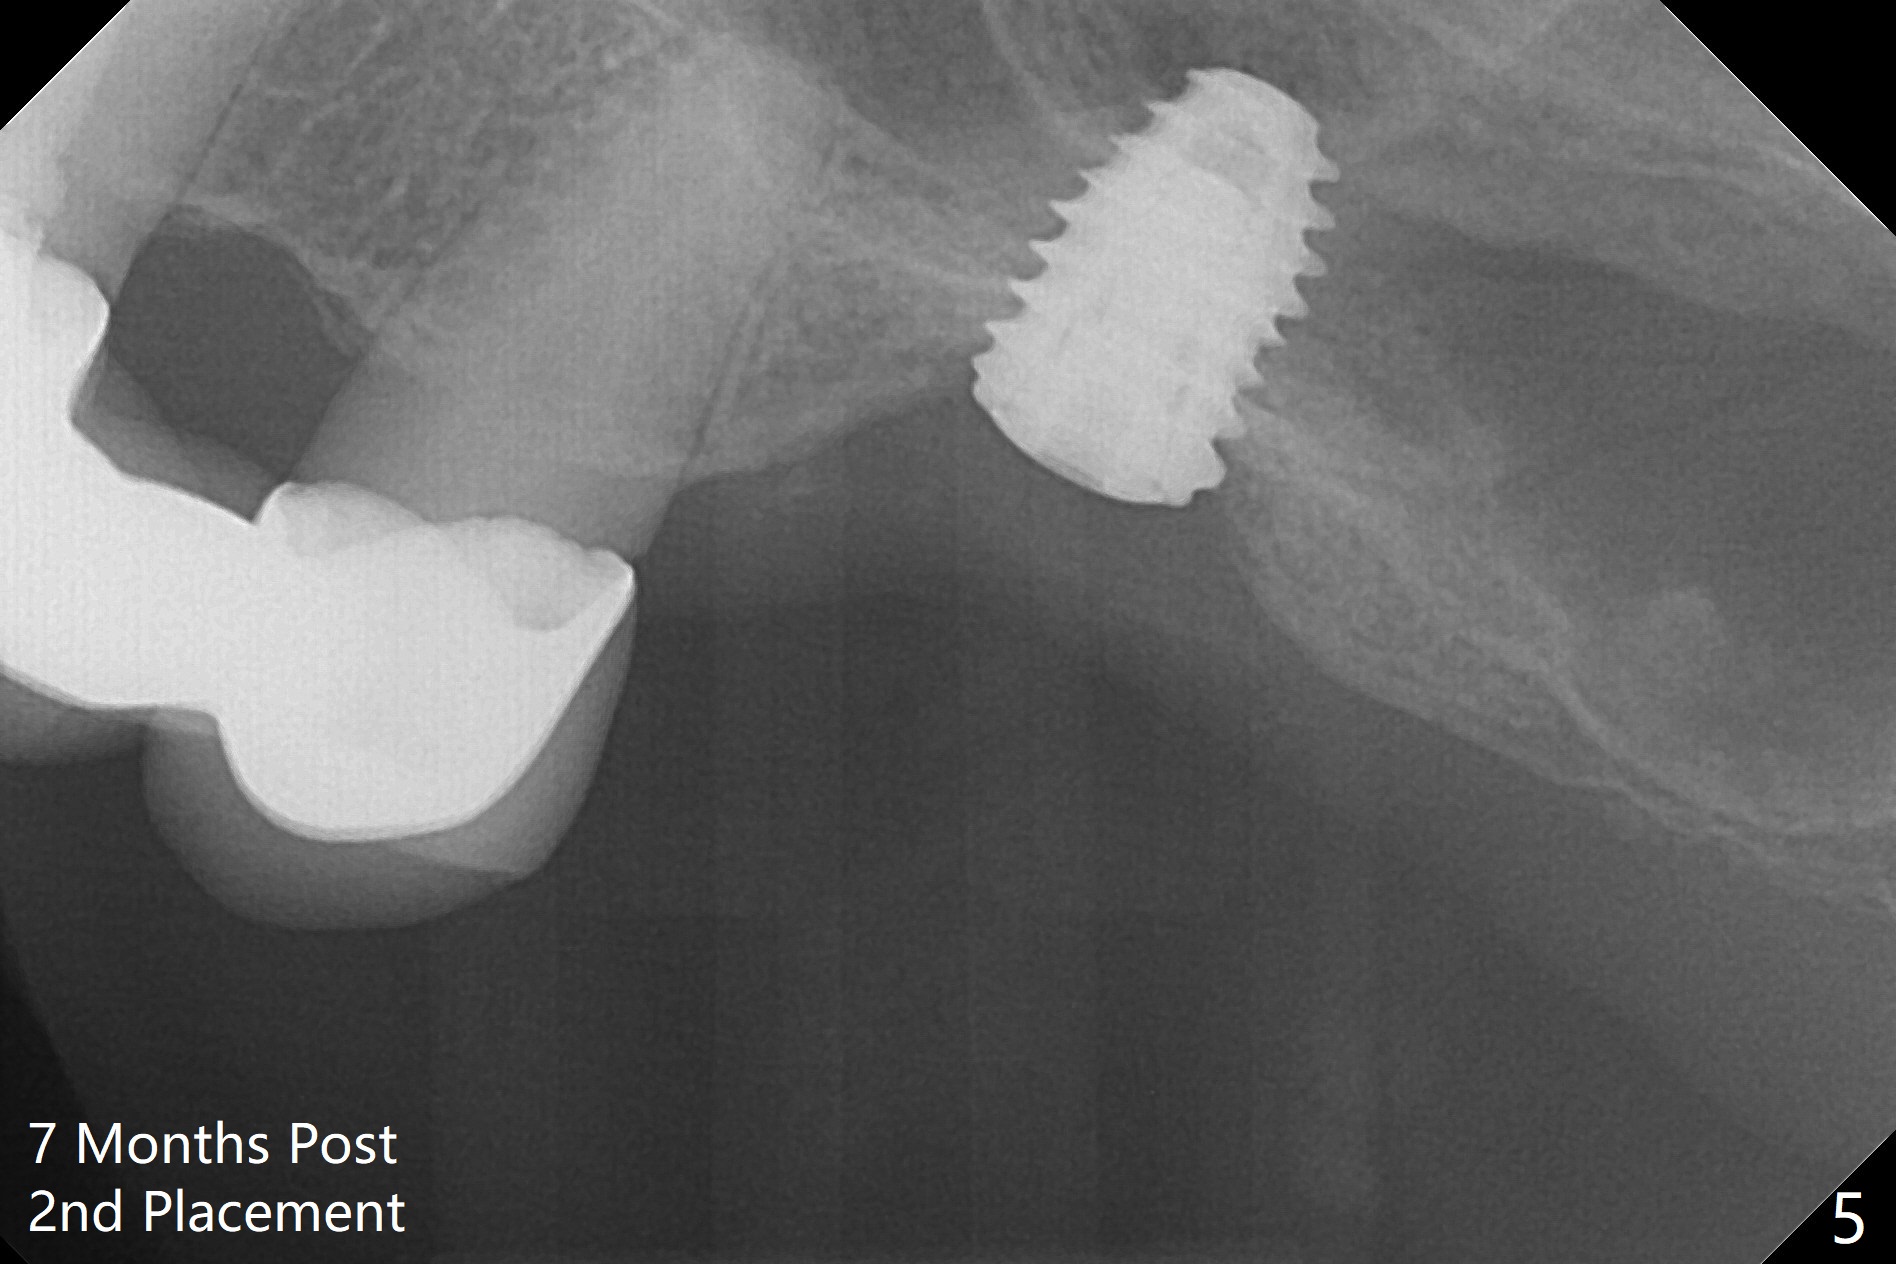

When the non-osteointegrated implant is removed, the sinus membrane is found to have been perforated. There is a history of clear discharge immediately postop ~ 1 year ago. Against the common wisdom, a 5x10 mm dummy implant is inserted with intention to correct the trajectory and 50 Ncm (Fig.1). With placement of Osteogen plug (presumably for repair of the perforation) and limited amount of Vanilla at the osteotomy, a 5x7.3 mm IS implant with SLA surface treatment is placed (Fig.2, ~ 40 Ncm). When the implant is further seated (Fig.3 arrow with bone graft coronally *)), its trajectory is within the normal limit (Fig.4 blue line). If the implant fails again, it must be due to the mild sinus infection. Bone graft, or preferably Osteogen Plug (collagen with osteoconductive ability) should have been done first. Mild tenderness exists with use of Water Pik 7 months post 2nd placement (Fig.5). Uncover shows that the implant is stable. A 6x3 mm healing abutment is placed. Next appointment a temporary crown will be fabricated for progressive loading. The abutment screw needs retightening 8 months post cementation, probably related to poor crown/implant ratio and missing 2nd molar (Fig.6).